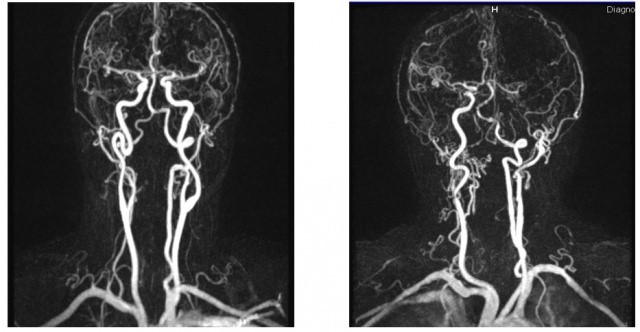

Ангиография позвоночных артерий при гипоплазии

Первым делом требуется первичный осмотр врачом-терапевтом, вертебрологом или сосудистым хирургом. На приеме врач соберет анамнез и проведет различные тесты (например, позу Ромберга ).

Следующим этапом является проведение ультразвуковой диагностики позвоночных артерий. Данный метод визуализации позволяет увидеть сужения или компрессию (сдавливание) сосудов, а также оценить скорость кровотока в них.

Наличие подозрений на гипоплазию по данным УЗИ – повод для проведения более точной и информативной диагностики. Для этого используется магнитно-резонансная томография в режиме ангиографии или компьютерная томография с контрастом.